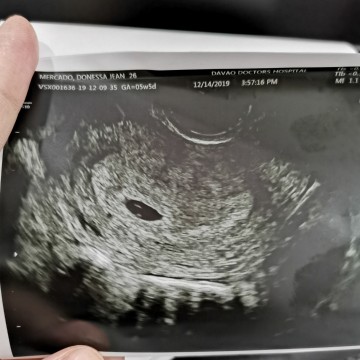

5 Weeks 5 Days, No Fetal Pole Ang YS

Nka try po ba kayo na 5 weeks 5 days na pero di parin ma identify ang loob ng GS?, ???